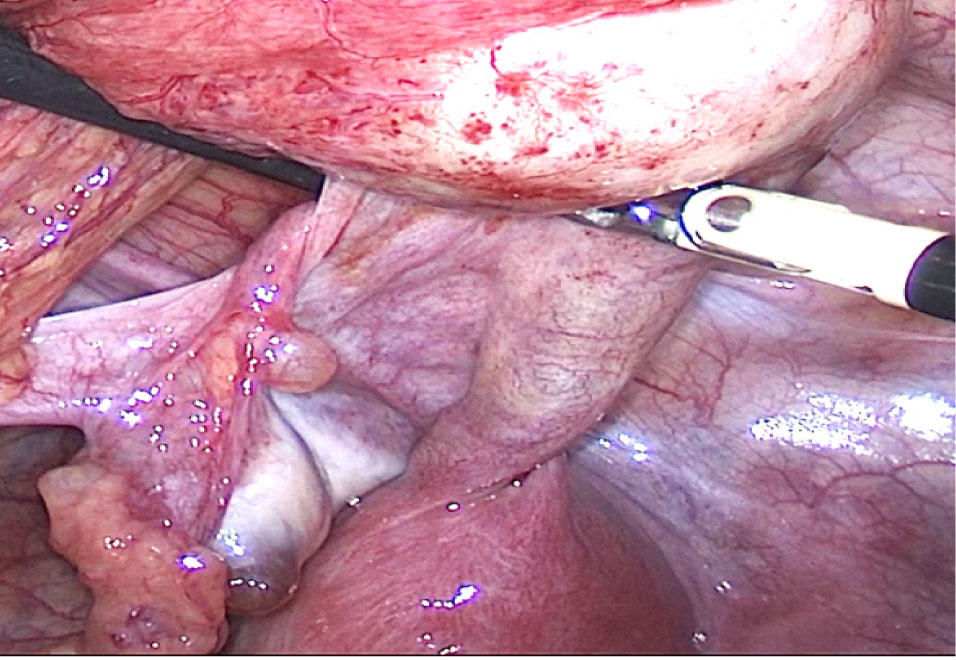

24.09.2024 г. выполнена диагностическая лапароскопия, интраоперационно обнаружено: тело матки представлено состоятельным правым маточным рогом размерами около 5 × 4,5 см, имеющим шейку матки, к которой на уровне внутреннего зева подходят крестцово-маточные связки, и интимно прилегающим к нему замкнутым левым маточным рогом округлой формы около 4 см в диаметре, слепо заканчивающимся на уровне внутреннего зева. От левого рога матки отходит отечная маточная труба, расширеннная в истмическом отделе до 3 см и в ампулярном отделе до 6 см, слепо заканчивающаяся – напряженный гематосальпинкс. К левому яичнику прилежит рудиментарный фимбриальный отдел левой маточной трубы, связанный с гематосальпинксом соединительнотканным «тяжем» (рис. 3, 4).

Рис. 3. Диагностическая лапароскопия. Аномалия развития матки

Рис. 4. Диагностическая лапароскопия. Рудиментарный фимбриальный отдел левой маточной трубы, соединенный с гематосальпинксом

В связи с обнаруженным решено выполнить сальпингэктомию слева, удаление рудиментарного левого рога матки. Сальпингэктомия выполнена типично. Выполнено удаление левого рудиментарного рога матки (извлечен методом морцелляции в стерильном контейнере). Ложе маточного рога ушито непрерывным швом (рассасывающаяся нить V-lock) (рис. 5).